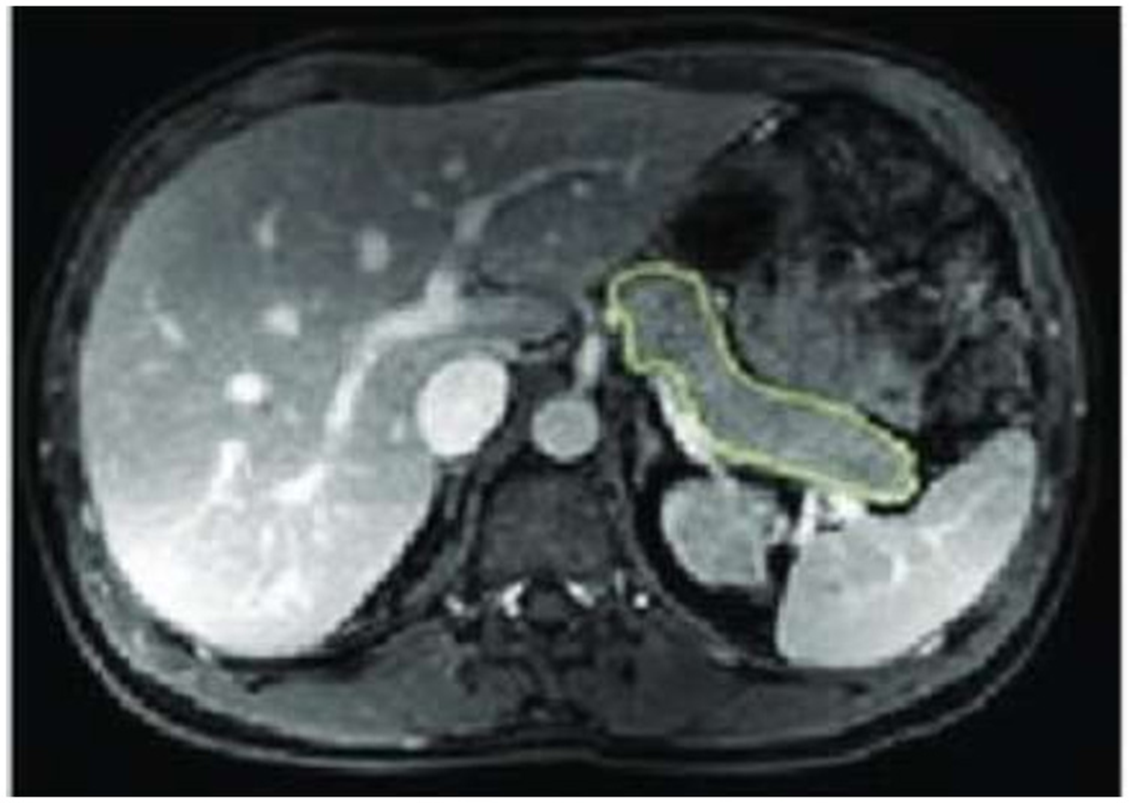

MRI of the abdomen was performed immediately before and 12 months post LSG, and no contrast media were given. Each subject was scanned once after a 10-h overnight fast in a 3 Tesla Ingenia scanner workstation (MR Systems Ingenia 3.0T, Philips Healthcare, Germany) in the supine position that first involved a set of localizer images. We employed a “Single Shot Fast Spin Echo,” which is a 3-plane localizer. Then, a respiratory-triggered T2–weighted 3D transverse fast spin-echo (TSE) sequence combined with a 2-point Dixon sequence was done. The pancreas was specified on each slice based on typical anatomical landmarks (19). Organ size was outlined by hand in each transaxial plane using OsiriX (OsiriX v.4.1, 32-bit, Pixmeo SARL), as shown in Figure 1.

Figure 1. Abdominal MRI showing pancreatic size drawn by hand in the transaxial plane.